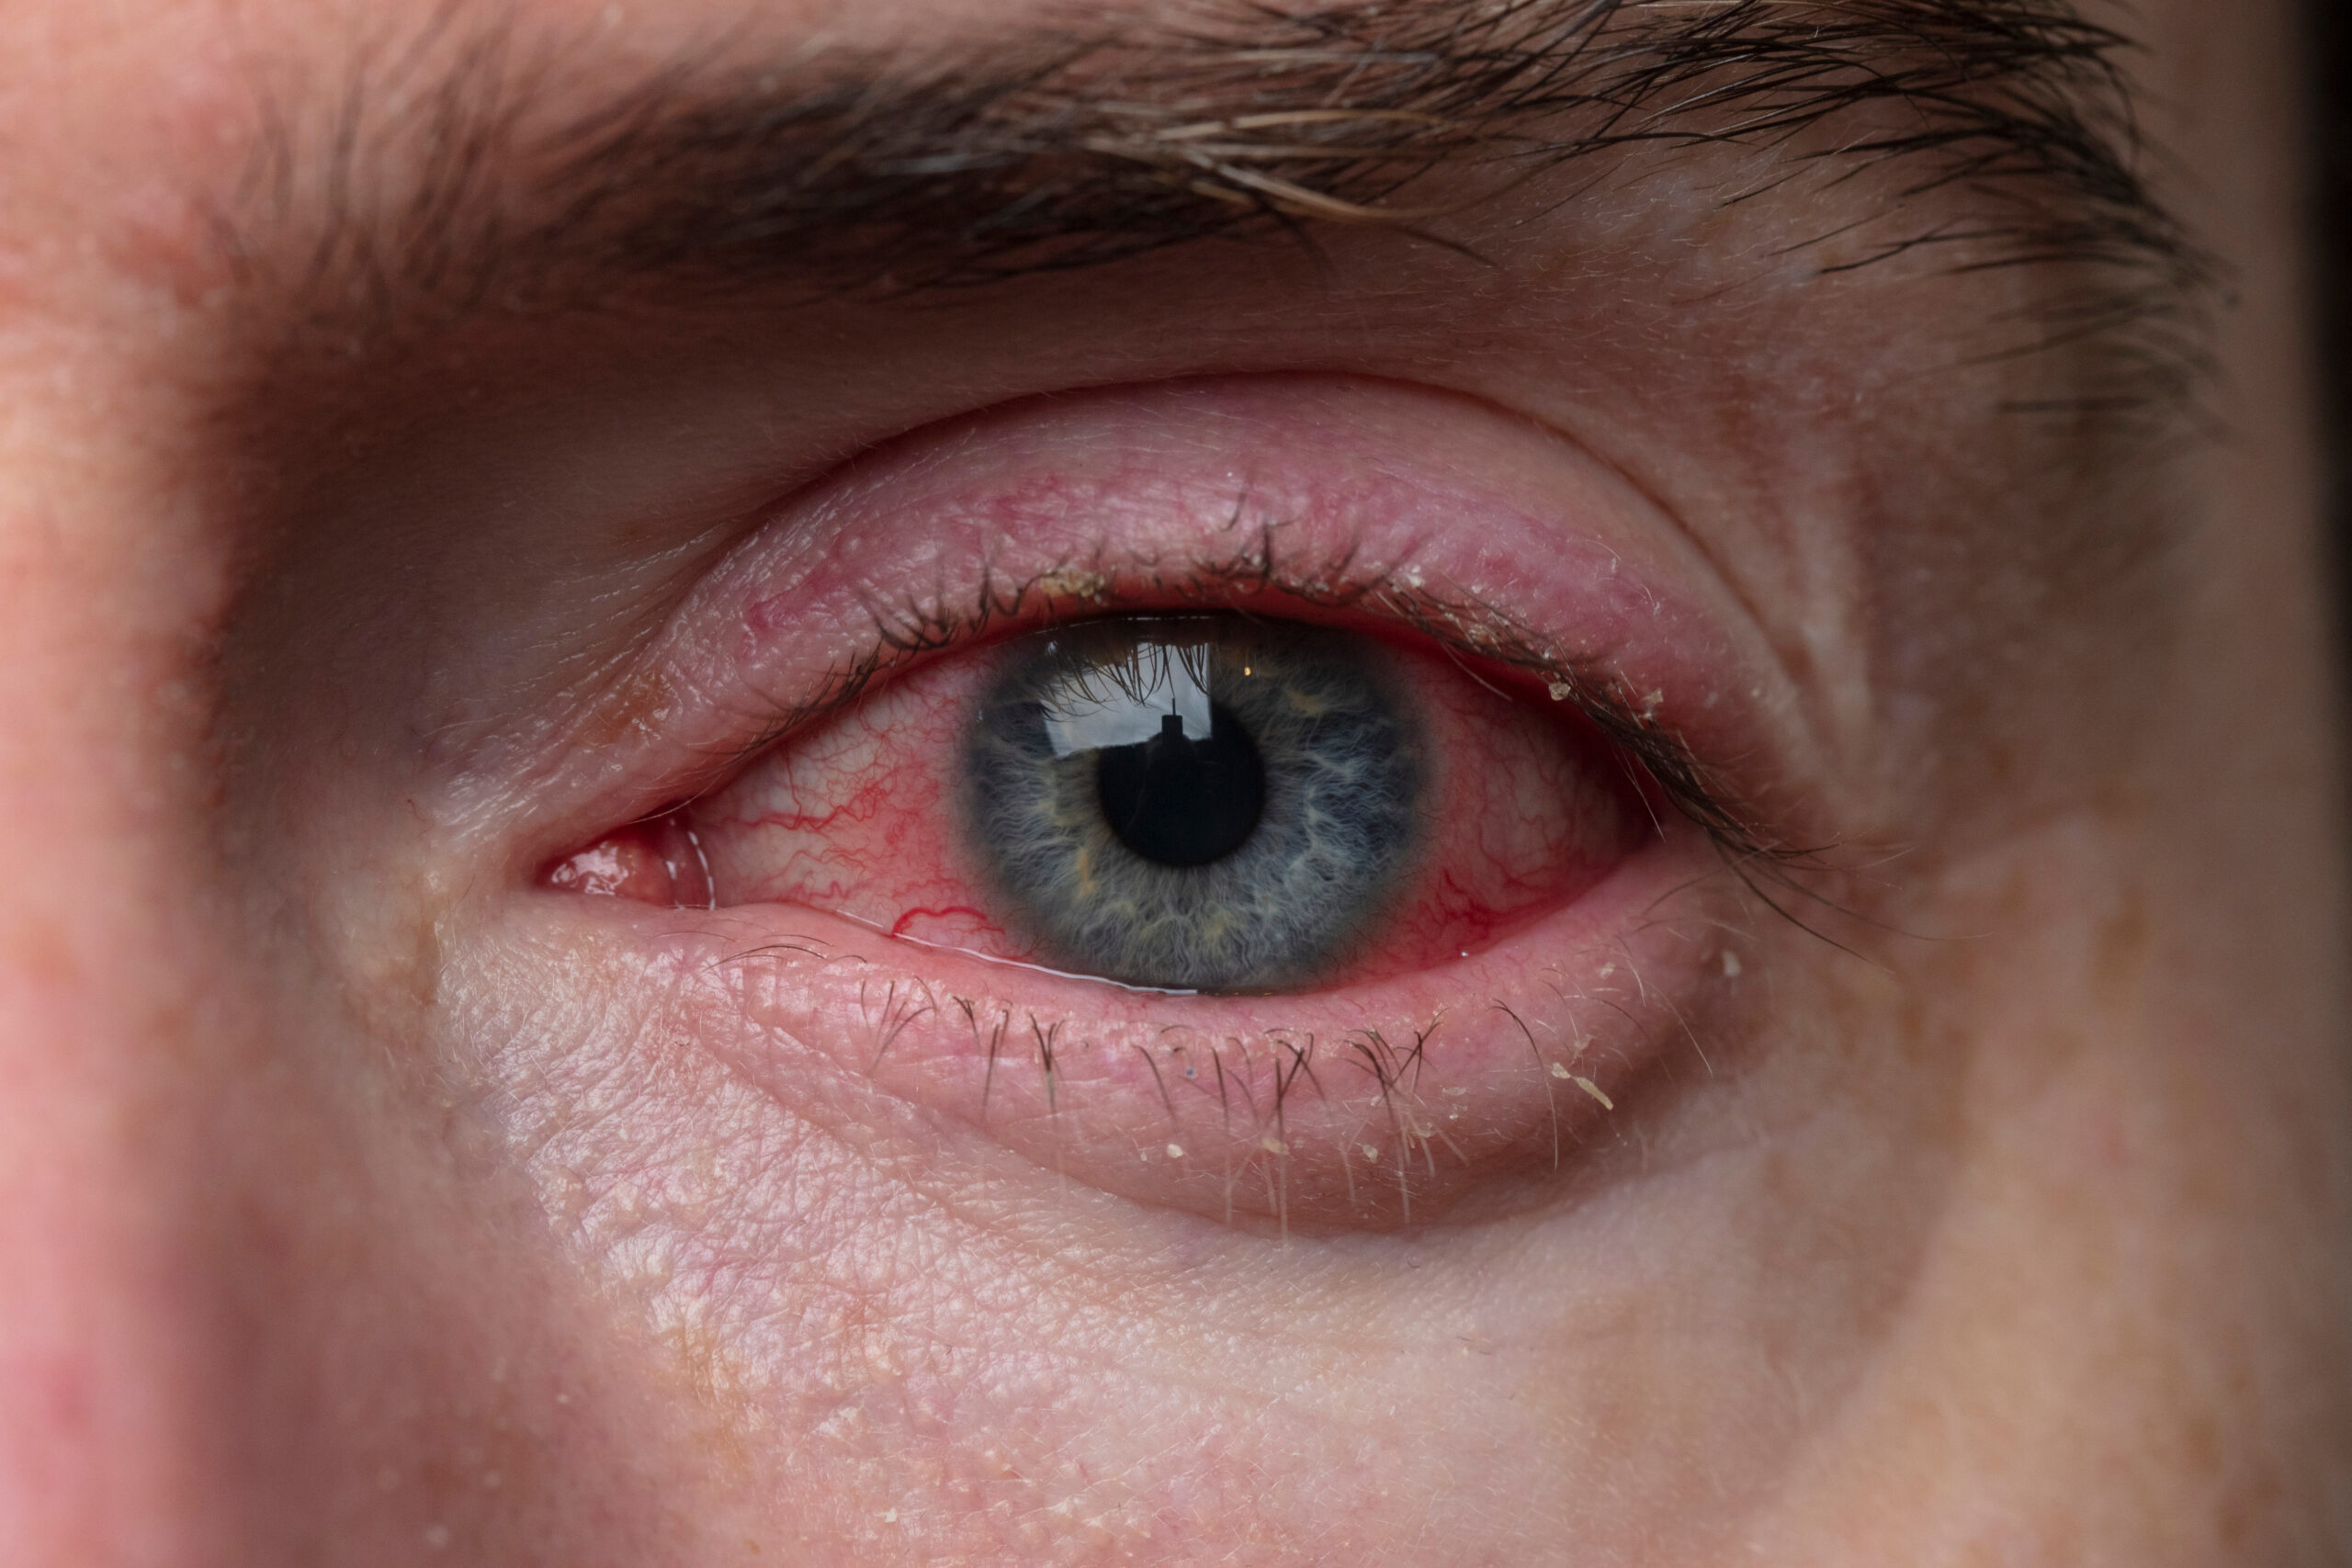

So one can imagine the chaos that ensues when disruption of these functions is triggered – poor vision quality (blurred), exposed cornea nerves (pain) and a tsunami of inflammation (redness + discharge).

Dry eye syndrome may have no symptoms very early on, but as the condition progresses the symptoms mount and may include:

▪ Red eyes

▪ Gritty or foreign body sensation

▪ Blurred vision

▪ Watery/Mucous discharge (this paradox occurs because the eye overcompensates in an attempt to mitigate dry eyes)

▪ Eyelash crusting/discharge

▪ Puffy eyelids

▪ Light sensitivity

WHAT ARE THE SYMPTOMS OF A BLEPHARITIS

Blepharitis, like Dry eye syndrome, may have few/no symptoms in the early phases, but these gradually mount as the disorder escalates:

▪ Red eyes

▪ Gritty or foreign body sensation

▪ Blurred vision

▪ Watery/Mucous discharge (this paradox occurs because the eye overcompensates in an attempt to mitigate the dry eyes)

▪ Eyelash crusting/discharge

▪ Puffy eyelids

▪ Light sensitivity